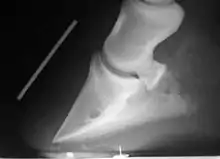

Radiographie d'une fourbure, avec le basculement de la troisième phalange du pied.

À l'état sauvage ou domestique, le cheval peut-être affecté par des parasites et des maladies telles que le tétanos, la grippe équine[112], la rage[113], la gourme, différentes affections respiratoires (emphysème…) et l'anémie infectieuse des équidés[114]. L'une des maladies les plus « classiques » chez le cheval est la fourbure, qui peut avoir différentes causes et se traduit par de vives douleurs au niveau des pieds[115]. La myoglobinurie, ou « maladie du lundi », et le « coup de sang » affectent les chevaux mis au travail dans de mauvaises conditions[116]. Les coliques, des troubles du système digestif, sont particulièrement dangereuses et difficiles à soigner et à prévenir, rendant nécessaire un contrôle strict de l'alimentation du cheval domestique[117]. Les maladies cardiaques, circulatoire, nerveuses, et les « vices d'écurie » n'affectent que les chevaux domestiques dans certaines conditions[118]. Les déformations permanentes du corps du cheval sont appelées des tares[119]. Toute affection de la locomotion est nommée boiterie, les causes possibles en sont nombreuses[120].